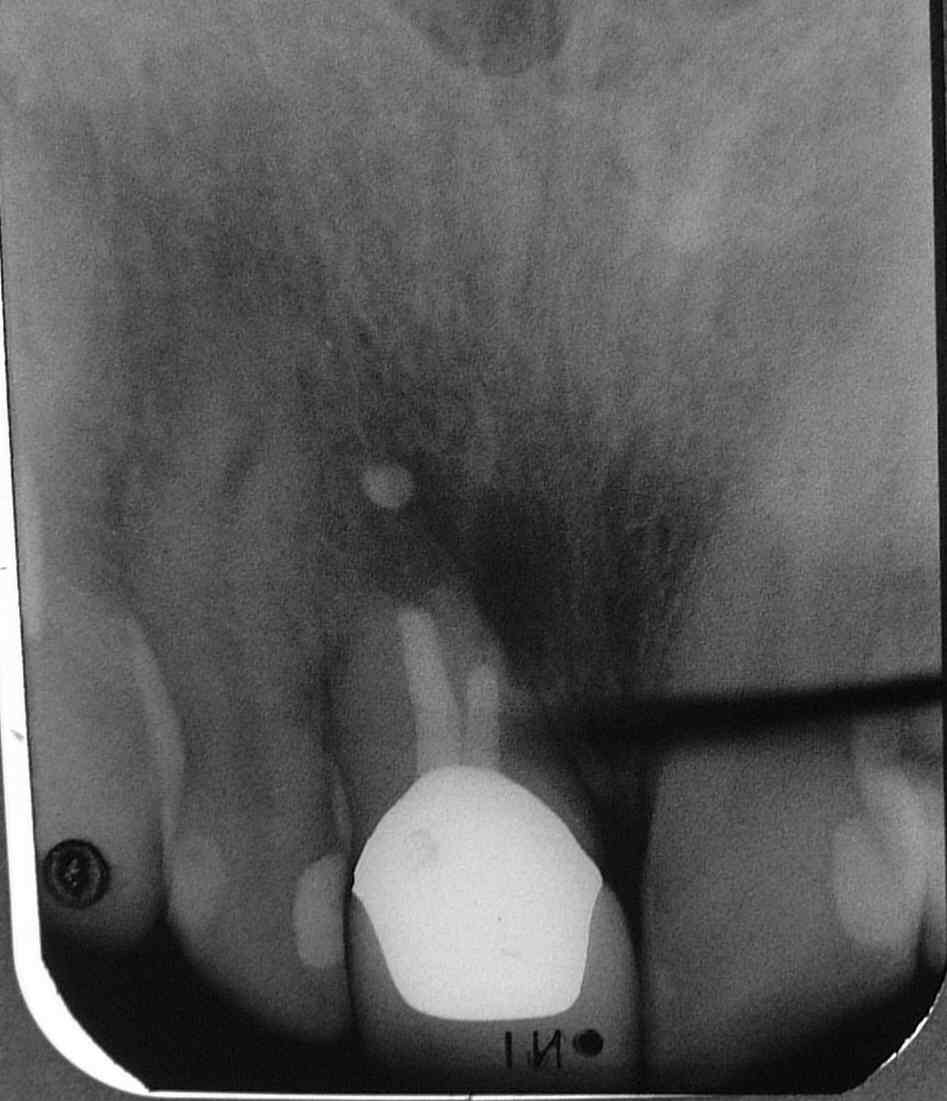

Zum Beispiel dieser Fall: Zustand nach WF vor vielen Jahren. Stiftaufbau in via falsa. Kroneversorgung. WSR vor wenigen Jahren  nach schmerzhafter Exazerbation. In 2006 wieder Exazerbation mit beginnender Abszessbildung vestibulär und L=II.